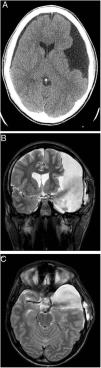

ResultsOur series comprised 13 males and 7 females (mean age: 64.6 months, range: 4–172 months). The most frequent site was suprasellar-prepontine (7), followed by intraventricular (6), quadrigeminal (3), interhemispheric (2) and Sylvian (2).

The procedure was successful in 60% (12/20) of the patients in the series. Success by location was 57% (4/7) in suprasellar cysts, 33% (1/3) in quadrigeminal cysts, 66% (4/6) in intraventricular cysts, 100% (2/2) in interhemispheric cysts and 50% (1/2) in Sylvian cysts. Treatment thus failed in 8 cases, with a mean time to failure of 12.12 months (range: 0–45 months). A new neuroendoscopic procedure was performed in 4 of these 8 cases (success in 2/4), a ventriculoperitoneal shunt was placed in 2 cases, a cystoperitoneal shunt was placed in 1 case and the remaining case was managed conservatively. Mean follow-up time was 52.45 months (range: 3–129 months).